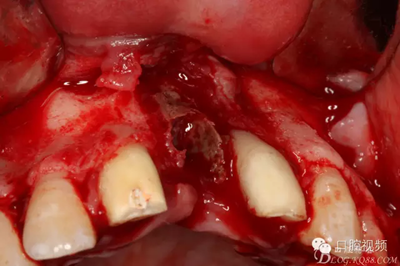

【原創(chuàng)博客】烤瓷橋下的悲劇-張東星